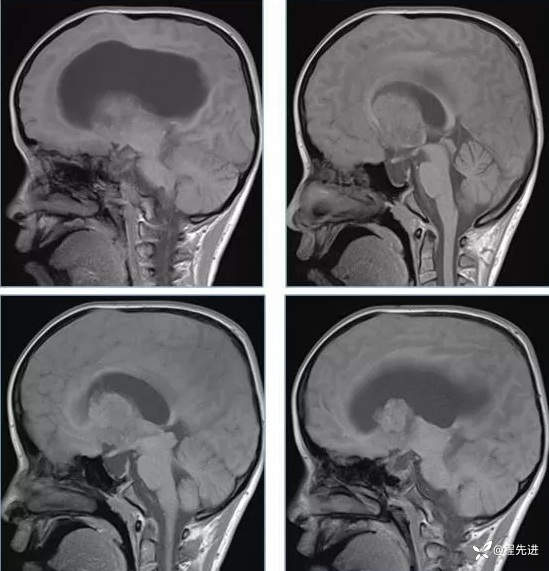

【神经】特别精彩病例|行走不稳2月余

患者性别:男

患者年龄:13岁

主诉:行走不稳2月余

现病史:2个月前患者无明显诱因下出现行走不稳,近期症状逐渐加重,站立不能。病程中患者无意识障碍,无头痛头晕,无明显恶心呕吐、视物旋转、耳鸣、眼球活动障碍等,无尿量增多、泌乳、口干等,体重无明显改变,睡眠可,食欲可,二便正常。

既往史:患者生后8个月和今年出现两次癫痫发作,持续时间不长

个人史:患者自幼失语,智力障碍

专科检查:右侧肢体肌力III-IV级,左侧肢体肌力IV级,肌张力下降